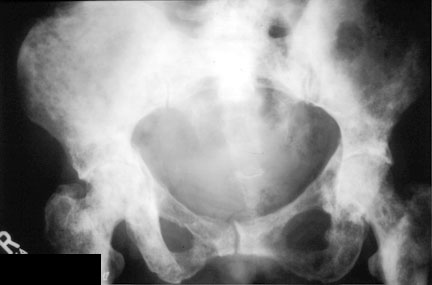

DiffuseMetsPelvis:

diffuse sclerotic metastases to the pelvis, sacrum and femurs